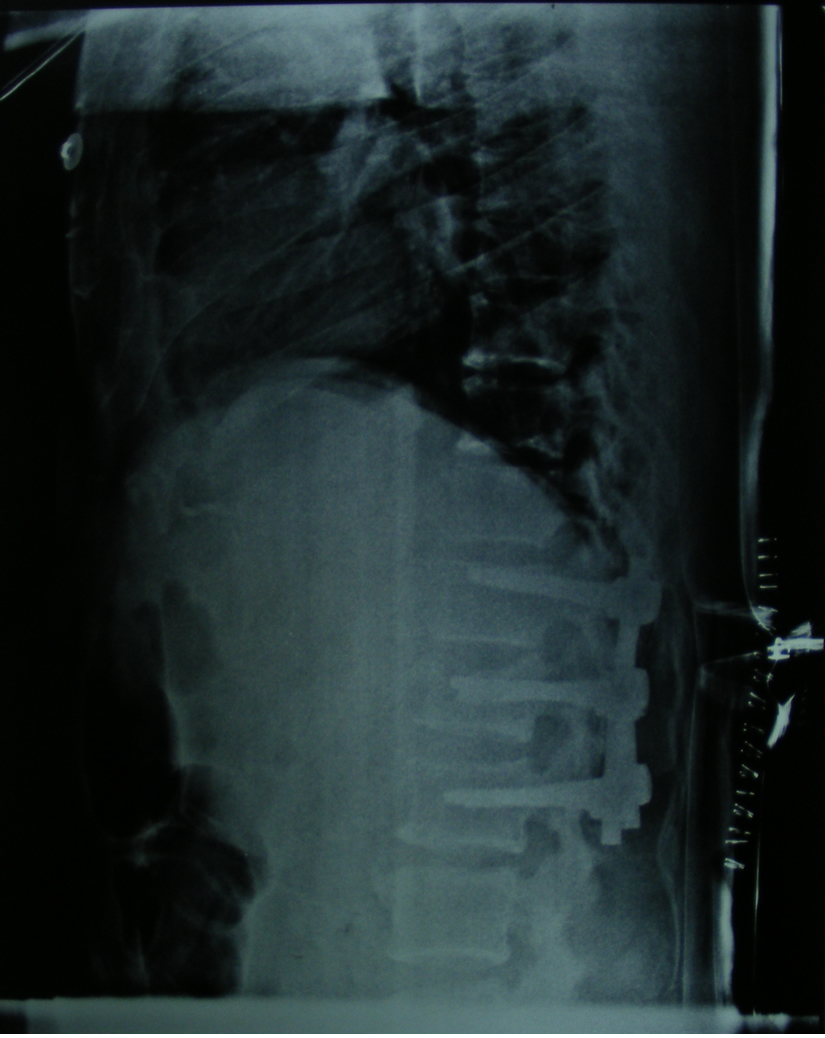

Eğer travma ilerleyen dönemde deformiteye yol açmayacaksa veya sinirlere baskı yaparak nörolojik bulguya neden olmadıysa korse ile tedavi edilebilir. Bu amaçla sert polietilen korseler ya da metalden yapılmış çerçeve tipi korseler kullanılabilir. Omurganın ağır zarar gördüğü durumlarda ileride oluşabilecek deformiteyi engellemek için omurganın vida ve çubuklarla sabitlenmesi gerekebilir. Nörolojik bulgu oluşturan bir kemiksel bası varsa, aynı seansta bu bası da ortadan kaldırılabilir.